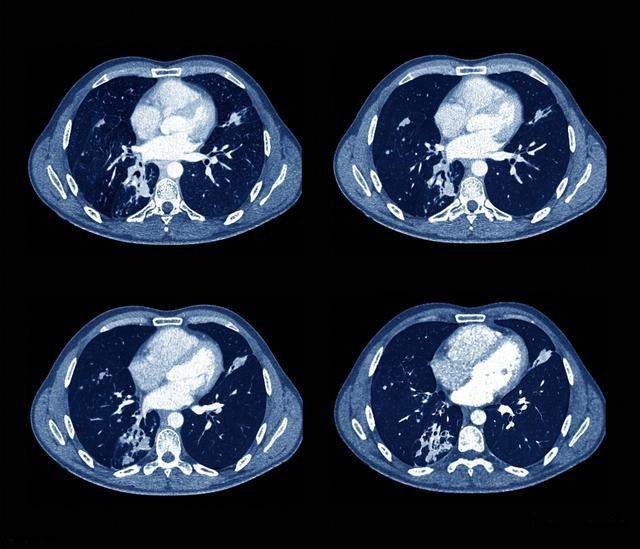

咯血是指喉部以下的呼吸器官(即气管、支气管或肺组织)出血,并经咳嗽动作从口腔排出的过程。咯血并不一定就是患癌,咯血原因太多了,癌症只是其中一种原因。癌症也并不是都会咯血,即便是肺癌,出现咯血症状的病人也是非常少的。在肺癌的几种类型中,肺鳞癌及小细胞肺癌发生咯血的几率相对于肺腺癌要大。这是因为鳞癌及小细胞癌中央型居多,病灶靠近肺门处,肺门周围血管丰富,肿瘤侵犯血管引起出血,并从支气管排出。中央型肺癌病人如果肿瘤侵犯毛细血管或小血管可出现痰中带血,侵犯大血管可能会出现大咯血引起窒息。

呼吸系统疾病:除了肺癌,肺结核、支气管扩张、肺脓肿等都可能会有咯血症状。对于年轻人出现咯血、低热、咳嗽、盗汗等症状时,要警惕肺结核可能。肺脓肿、肺炎这些炎症可导致支气管黏膜或病灶毛细血管渗透性增高,或黏膜下血管壁溃破,从而引起出血。

2.循环系统疾病:常见的有风湿性心脏病二尖瓣狭窄、高血压性心脏病、肺动脉高压、主动脉瘤、肺梗死及肺动静脉瘘等。风心病二尖瓣狭窄病人由于侧支循环支气管静脉曲张破裂而出现咯血,出现急性呼衰时可出现粉红色泡沫痰,并发肺梗死时会出现暗红色血痰,并呈胶冻状。